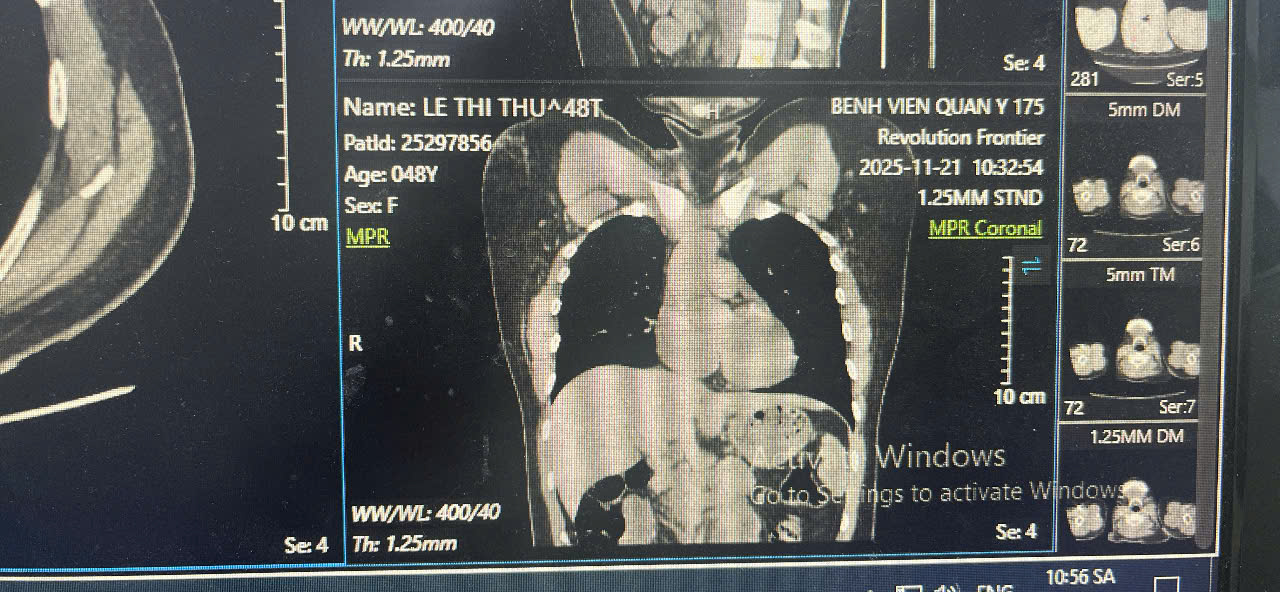

Hình ảnh CT-Scan sau khi rút dị vật

Ê-kíp đã lựa chọn phương pháp lấy dị vật qua đường tĩnh mạch đùi, tránh phẫu thuật mở ngực – mổ tim vốn tiềm ẩn nhiều rủi ro và thời gian hồi phục kéo dài. Dụng cụ snare chuyên dụng được đưa từ tĩnh mạch đùi lên tĩnh mạch chủ dưới, vào nhĩ phải, qua van ba lá đến thất phải và tiếp cận động mạch phổi. Tại vị trí phân nhánh động mạch phổi, một điểm rất khó tiếp cận, ê-kíp đã gắp chính xác đoạn catheter bị đứt và đưa ra ngoài an toàn.

Nhờ kỹ thuật ít xâm lấn, ca can thiệp diễn ra thuận lợi, bệnh nhân tỉnh táo ngay sau thủ thuật, hồi phục tốt và xuất viện sau theo dõi ngắn.